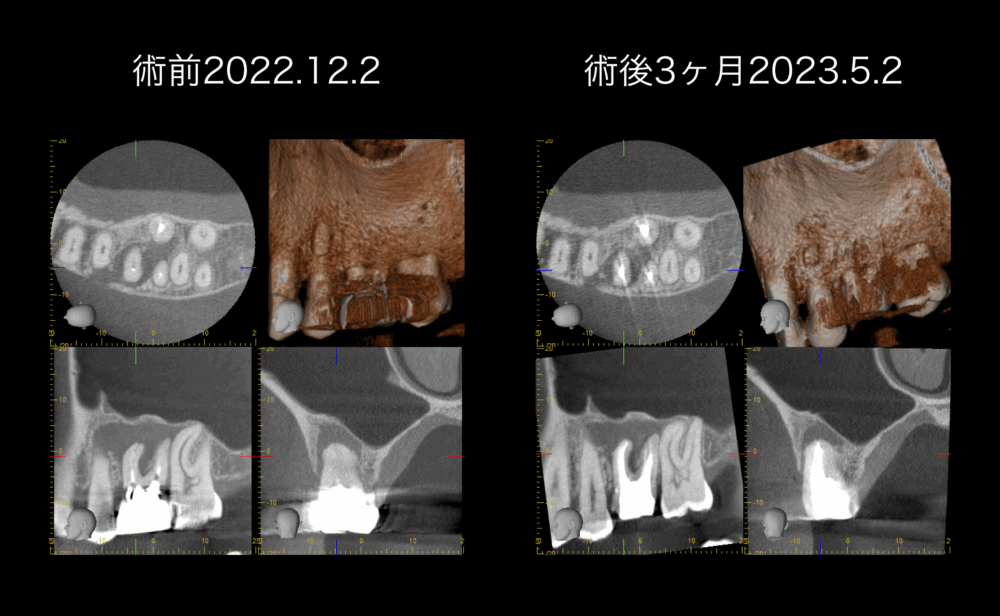

術後3ヶ月経過時点でのデンタルを術直後と比較しても、根尖部透過像の境界が不明瞭なので、CTを撮影しました。

axial画像(CT画像左上)を比較すると、根尖部透過像は、縮小しています。また、右上の3D画像から、左上顎第二小臼歯根面の露出範囲が小さくなっています。頬側皮質骨の断続範囲が縮小しています。